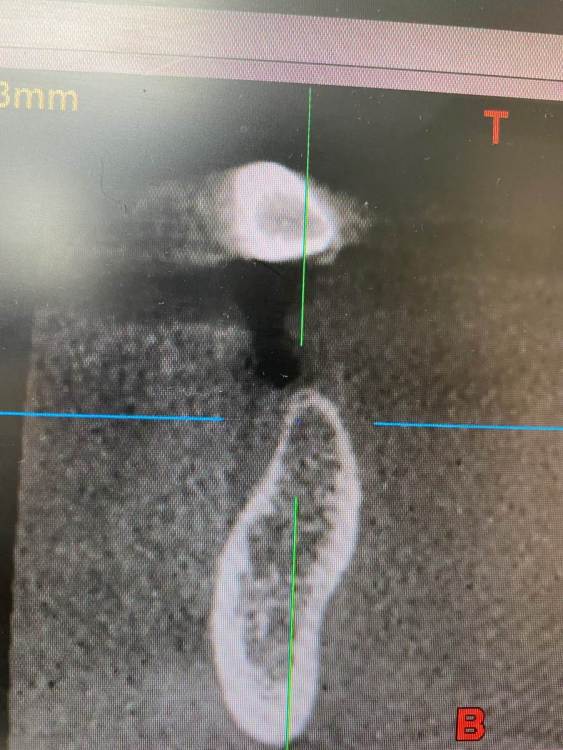

колесников Опубликовано 6 июля, 2022 Поделиться Опубликовано 6 июля, 2022 Здравствуйте коллеги! Впервые вижу перелом Астры. Впервые получил перелом «своей»Астры. Вероятно ещё никто не видел перелом Астры профайл. Диаметры 4.5 и 5.0. Самое неприятное что это произошло за 1,5 года. Ошибка протезирования. Перегруз. Резорбция. Фрактура. Из интересного. Одновременно с имплантацией была произведена контурная пластика поднадкостнично,графт шурос. Это работает. Ставим галочки и двигаемся дальше. 2 1 1 Ссылка на комментарий

Irouil Опубликовано 7 июля, 2022 Поделиться Опубликовано 7 июля, 2022 Профайлы вроде бы 4.2 и 4.8 Ссылка на комментарий

колесников Опубликовано 7 июля, 2022 Автор Поделиться Опубликовано 7 июля, 2022 6 часов назад, Irouil сказал: Профайлы вроде бы 4.2 и 4.8 Это не ev,старые тх 4.5,5.0 1 Ссылка на комментарий

Irouil Опубликовано 11 июля, 2022 Поделиться Опубликовано 11 июля, 2022 (изменено) Не понял - почему недозаглубен? Оба винтыа где-то на 1мм под краем гребня Изменено 11 июля, 2022 пользователем Irouil Ссылка на комментарий

TIGER Опубликовано 11 июля, 2022 Поделиться Опубликовано 11 июля, 2022 @Irouil первое фото Ссылка на комментарий

Irouil Опубликовано 11 июля, 2022 Поделиться Опубликовано 11 июля, 2022 (изменено) По фото невозможно понять что там было заглубленно и что нет, на рентгене картина объективнее Я вижу из возможных косяков пл хирургии только избыточно лингвальное позиционирование платформы у одного из винтов, из-за чего стенка очень тонкая - если там случилась резорбция, то иллюзию недозаглубения на фото она вполне может создать К тому же, ТС раньше рассказывал что часто идёт на тунельную твердотканную аугментацию при имплантации в таких случаях, если тут тоже - то для меня неточное позиционирование объясняется именно тунельным подходом и ограниченным обзором по такому поводу. Это, в сущности, единственное, что останавливает меня самого попробовать подобную аугментацию как альтернативу минисосиджу. Но надо услышать ТС, это только мои догадки Изменено 11 июля, 2022 пользователем Irouil Ссылка на комментарий

Irouil Опубликовано 11 июля, 2022 Поделиться Опубликовано 11 июля, 2022 @TIGER какие у Вас на этом фото объективные ориентиры, позволяющие оценить уровень погружения импланта? Такие, чтобы были точно в одной плоскости с оцениваемым положением платформы и в параллельной плоскости к матрице камеры? Это же все равно что объем альвеолярного гребня в области альвеолярной бухты оценивать по плоскостным снимкам Ссылка на комментарий

TIGER Опубликовано 11 июля, 2022 Поделиться Опубликовано 11 июля, 2022 @Irouil ну тут много ума не надо и трёхмёрной информации,чтобы понять исходя из этого фото,что там изначальный недозаглуб был (платформа торчит на уровне десневого края),плюс фактор протетики возможно сыграл....? Ссылка на комментарий

Irouil Опубликовано 11 июля, 2022 Поделиться Опубликовано 11 июля, 2022 @TIGER ладно, давайте подождём мнения Игоря, на рентгене (который был ДО резорбции и явно объективнее, чем фото ПОСЛЕ неё, да ещё и не в академической проекции) я явного недозаглубения не вижу, хотя глубить, вроде бы, ещё было куда и тут вопрос скорее в том, почему ТС не решил перестраховаться 1 Ссылка на комментарий

Astronaft Опубликовано 12 июля, 2022 Поделиться Опубликовано 12 июля, 2022 (изменено) 06.07.2022 в 14:28, колесников сказал: Протокол отработан как автомат Калашникова,платформа относительно Зенита и вершины гребня,высота уступа,наличие и ширина прикреплённой слизистой. Далее процесс запускается вспять и через два года наблюдаем прирост кости на скосе гребня. Это хорошай заговор-пожелание. В жизни часто не так. По одной простой причине общее здоровье человека влияет намного сильнее. Пародонтологический статус - если есть карманы хоть 5-6мм где-то во рту риск пери-имплантных явлений возрастает. Микробиота слюны, вязкость, диета, качество гигиены, обший воспалительный фон- это сфера влияния пациента. Качественное местное исполнение это хороший фундамент - только одна из составляющих. Астра Профаил - укороченный, асимметричый конус. 3мм с одной стороны, 2мм с другой. Конфигурация перелома закономерна - сами абатменты раскололи высокую стенку от низкой. Я бы предположил что тещины первичны, резорбция это следствие. Изменено 12 июля, 2022 пользователем Astronaft 2 4 Ссылка на комментарий